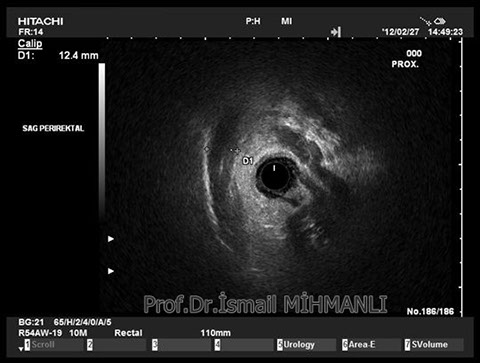

Crohn hastasında perirektal reaktif lenfadenopati